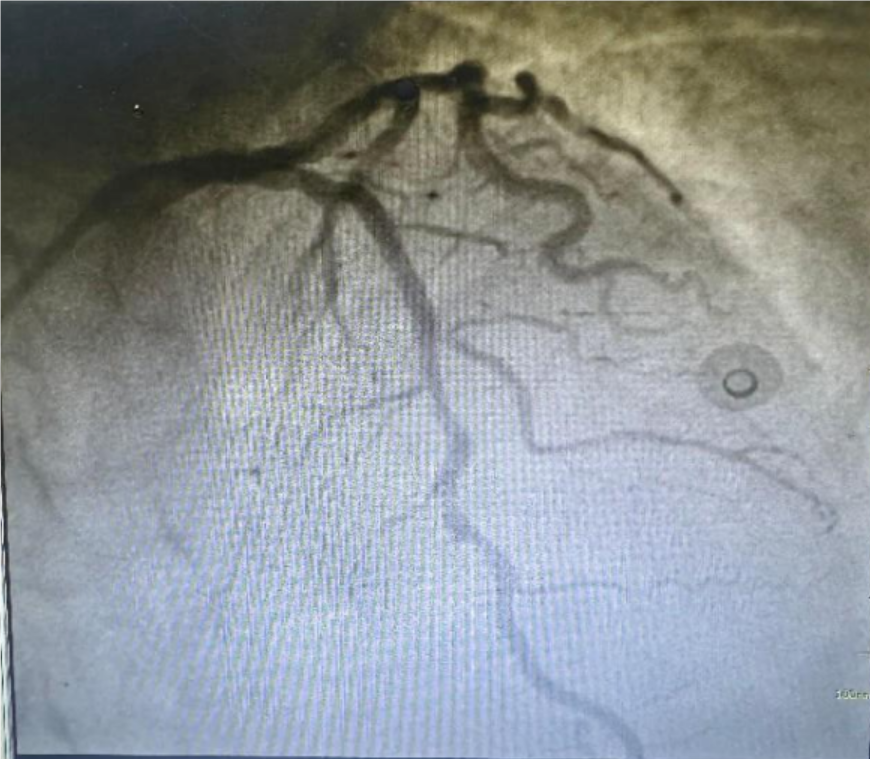

近日,东莞康华医院胸痛中心以高效的应急反应和专业的急救技能,成功救治了一名56岁的广泛前壁心肌梗死患者。从患者由救护车到达血管造影室门口到导丝通过,仅耗时11分钟,刷新了医院的最短救治纪录。经过心血管重症监护室医务人员的精心护理,患者目前已康复出院。家住东莞长安的周先生(化名),晚饭后突发胸口剧烈疼痛,伴有大汗淋漓和濒死感。家属迅速将其送至长安乌沙医院就诊。当晚10点40分接诊后,急诊科迅速完成了首份心电图,显示为急性广泛前壁心肌梗死。随即,医院开启了“超速救心”程序,患者在2小时内接受了必要的口服抢救药物。

东莞康华医院胸痛中心接到通知后,立即启动“双绕行”程序,即绕行急诊和绕行CCU,直接进入手术室。当晚23点43分27秒,救护车直接将患者送至血管造影室门口。23点49分,手术正式开始,仅用11分钟就完成了导丝通过闭塞血管的操作,被堵塞的血管恢复畅通,患者转危为安。此次救治行动中,“门丝时间”仅11分钟,再次刷新了医院胸痛中心的最短救治纪录。胸痛中心副主任揭英纯表示,这得益于严格按照胸痛中心建设培训的“双绕行”流程进行,最大程度地挽救了患者的心肌。